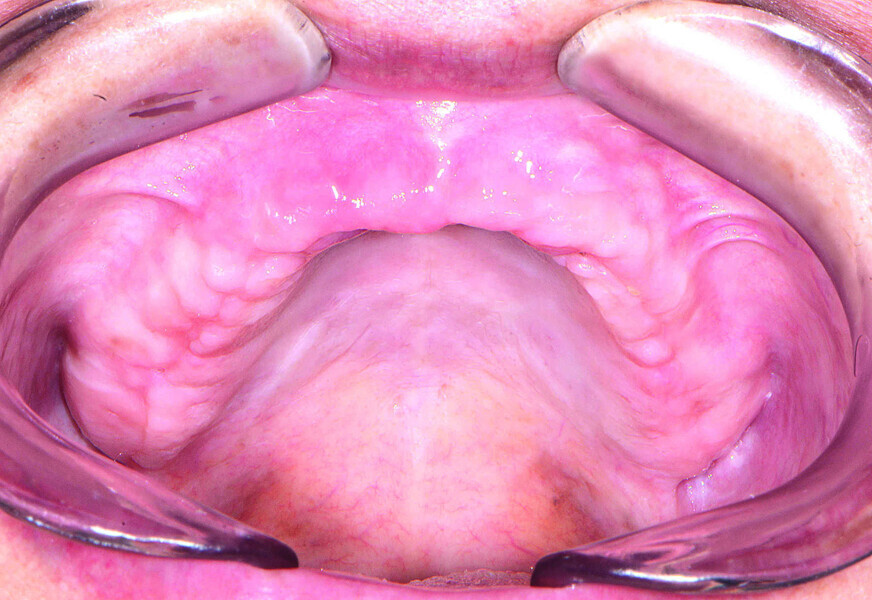

Fig 2 Vue préopératoire avec écarteur de lèvres, sans prothèse